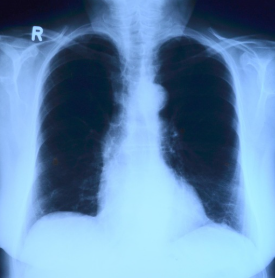

폐기흉은 폐의 공기주머니(폐포)가 터지면서 공기가 흉막강으로 새어 나와, 폐가 수축되는 질환입니다.

정상적으로는 폐가 공기를 들이마시고 내쉬면서 팽창과 수축을 반복하지만, 흉강 내 압력이 높아지면 폐가 펴지지 못해 호흡 곤란을 유발합니다.

전유성 씨의 경우, 과거 폐렴 이력이 있었고 고령으로 인해 폐 기능이 약화된 상태에서 폐기흉이 치명적으로 작용한 것으로 추정됩니다.